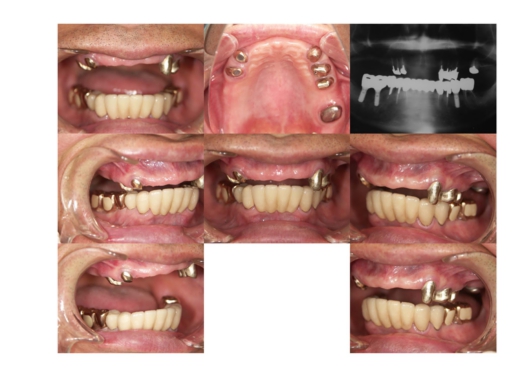

インプラントの症例集

当院で治療された方々の症例を

各科目ごとにご紹介します。

症例23

男性